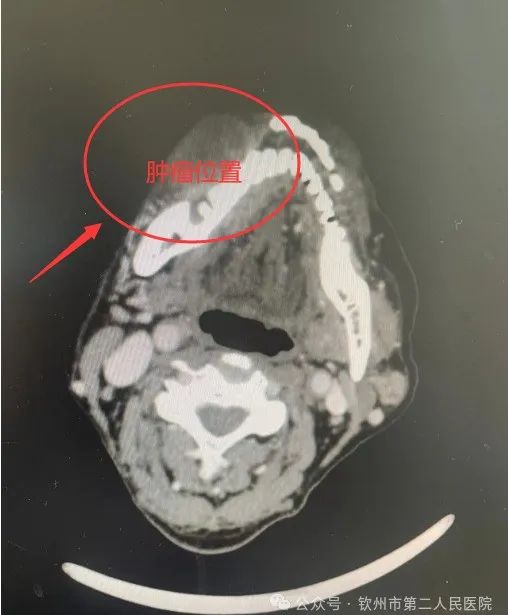

1个月前,62岁的程伯(化名)因右侧口颊粘膜长了巨大肿物出现反复口腔疼痛、张口受限,并出现反复出血。程伯来到我院耳鼻咽喉头颈外科二病区就诊,科主任吕忠对程伯的病情非常重视,立即对程伯的症状和体征进行详细分析,并完善了相关检查。肿物组织的病理检查回报:右侧口颊粘膜癌,CT提示肿瘤累及大部分右侧口颊粘膜。

为了尽量减轻程伯及家属的诸多顾虑,吕忠耐心详细的给他们讲解了手术的利与弊,最终程伯及家属同意手术。为了解决完整切除程伯口颊区肿瘤及修复封闭口颊区,手术团队针对程伯的病情结合术前CT、MRI等影像资料,对手术方案进行反复讨论和研究,最终选择行口颊粘膜癌扩大切除术+前臂游离肌皮瓣转移修复。由吕忠团队负责行肿瘤切除+颈淋巴结清扫,骨外科四区易广田主任团队同时制备前臂游离皮瓣,再由吕忠团队使用皮瓣塑形修复切除肿瘤后的口颊部内外面粘膜皮肤软组织的缺损。